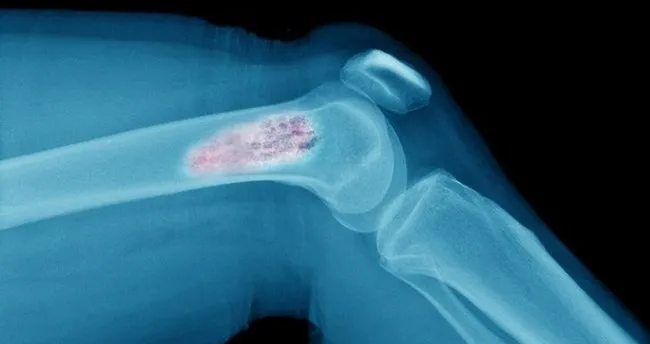

kemik kanseri nedir kemik kanseri belirtileri ve nedenleri nelerdir

kemik kanseri tumoru nedir ve belirtilerini gosteren 5 isaret

kemik tumorleri ve tedavisi

kemik kanseri tumoru nedir belirtileri nelerdir turleri nedir saglik ansiklopedisi

iyi huylu kemik tumoru nedir memorial

kemik kanseri nedir belirtileri nelerdir kemik kanseri neden olur kemik kanserinde olum riski ve iyilesme orani ne saglik haberleri

kemik kanseri tumor belirtileri nelerdir nasil anlasilir

kollarda ve bacaklarda sislik varsa dikkat kemik tumoru sinyali olabilir mahmure